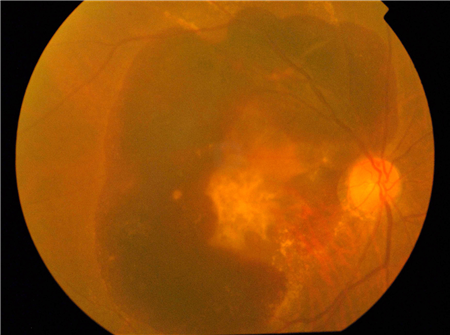

而另外一種濕性黃斑變性就需要引起重視了,因為濕性黃斑變性才是容易致盲的那個。濕性黃斑變性的形成原因,與脈絡膜出現異常新生血管有關,這些新生血管很容易發生滲漏和出血,如果未及時治療,血液以及滲出物將在黃斑區域聚集,可破壞黃斑區的感光細胞,對視力造成難以恢復的損傷,嚴重可致盲。

濕性黃斑變性的癥狀主要表現為:視物變形(如將直線看成曲線)、中央視力模糊、視野中央出現暗點或者盲點。但由于早期癥狀沒有特別明顯,很多老年人都誤以為是自己老眼昏花,而未引起重視,因而耽誤好的治療時機。